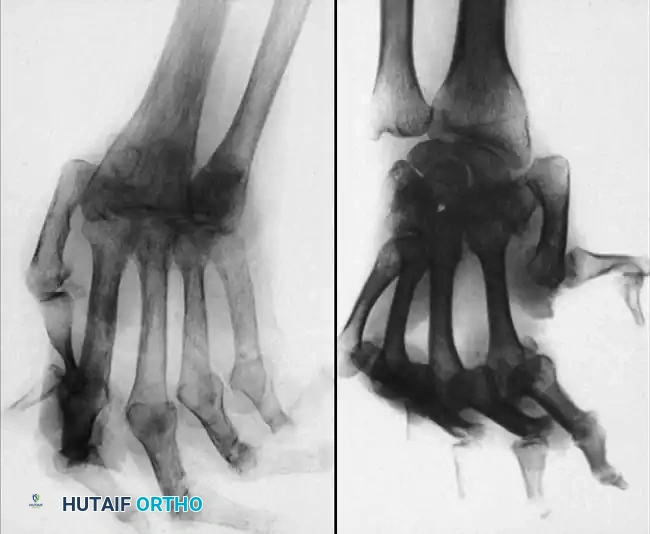

Fig. 70-6 A and B, Typical radiographs of hand and wrist in patients with systemic lupus erythematosus. Note joint dislocations without erosive changes or joint space narrowing. (From Nalebuff EA: Surgery of psoriatic arthritis of the hand, Hand Clin 12:603, 1996.)